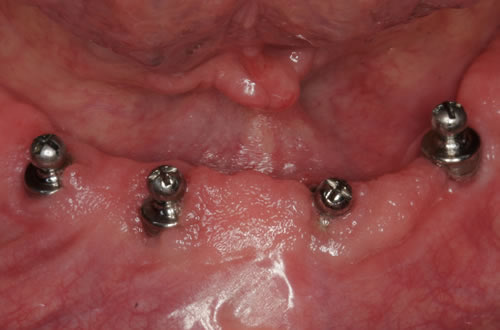

Abb. 3.5: Kugelknöpfe im Mund.

Abb. 3.6: Prothesenansicht von unten mit eingearbeiteten Sekundärteilen.

Diese Beispiele ließen sich endlos fortführen. Sie zeigen die Probleme bei der Versorgung zahnloser Kiefer, wie sie immer wieder geschildert werden. Mit Hilfe sehr einfacher Maßnahmen kann durch die Einpflanzung künstlicher Zahnwurzeln eine instabile Prothese soweit befestigt werden, dass die Kau- und Sprechfunktion wieder hergestellt ist. Manchmal kann die alte Prothese weiterverwendet werden, in dem man in die Prothesenbasis Sekundärteile einarbeitet, die für Halt sorgen (Abb. 3.5, 3.6). Bei aufwendigeren Steg- oder Teleskoparbeiten muss auch der Zahnersatz der auf den Implantaten fixiert wird neu angefertigt werden. Diese Arbeiten werden dann brückenartig und sehr grazil gestaltet. (Abb. 3.7 bis 3.12).